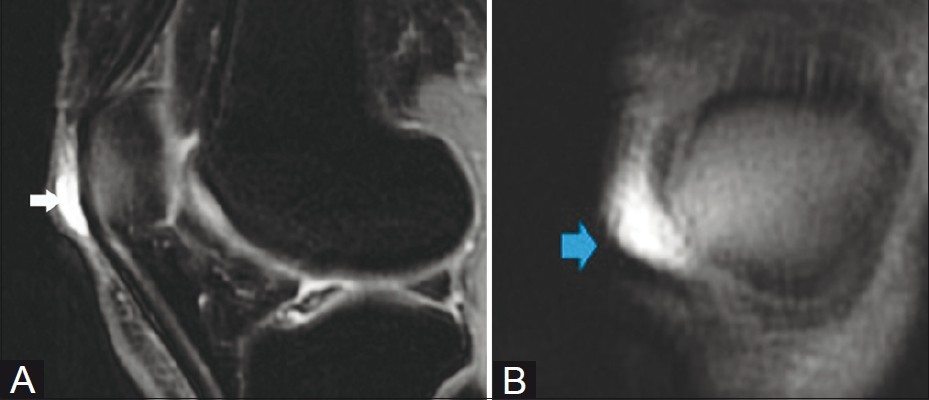

대부분의 정상적인 점액낭은 소량의 점액을 함유하여 MRI에서 잘 관찰되지 않지만, 염증성 변화에 의해 점액양이 증가되면 T1 영상에서 저신호 강도를, T2 영상에서 고신호 강도를 보이는 경계가 명확한 점액낭이 관찰된다.

△ 거위발 점액낭염(Pes anserine bursitis)의 MRI 소견

△ 내측측부인대 점액낭염(Medial collateral ligament bursitis)의 MRI 소견